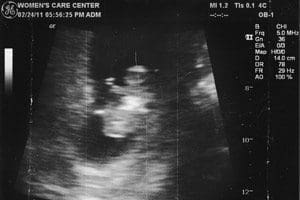

Mareza has the first image taken of Joseph, too, the one from earlier in the day on Feb. 24, 2011, the one taken during her initial consult in preparation for the abortion at Affiliated Medical Services on Farwell Avenue in Milwaukee.

That one is even fuzzier and is taken at a wider angle. Here it’s more difficult to see Joseph and he looks more like the mass of cells that Mareza thought he was at this 10-week stage of her pregnancy.

“Those words were with her for the rest of her visit and he was right. There is another person here,” explained Irma Landeros of her daughter’s reaction to Miller’s comment.USEsscans110-B2-CopyMareza Landeros had two ultrasounds performed on her on Feb. 24, 2011 when she was about 10 weeks pregnant. The first, performed at Affiliated Medical Services, Milwaukee, an abortion clinic, is at top. Its wide angle image makes it difficult to distinguish features of the unborn baby. Later the same day, the second image was taken at the Women’s Care Center, located across the street. Its more focused image shows distinctive features and limbs of the unborn child.